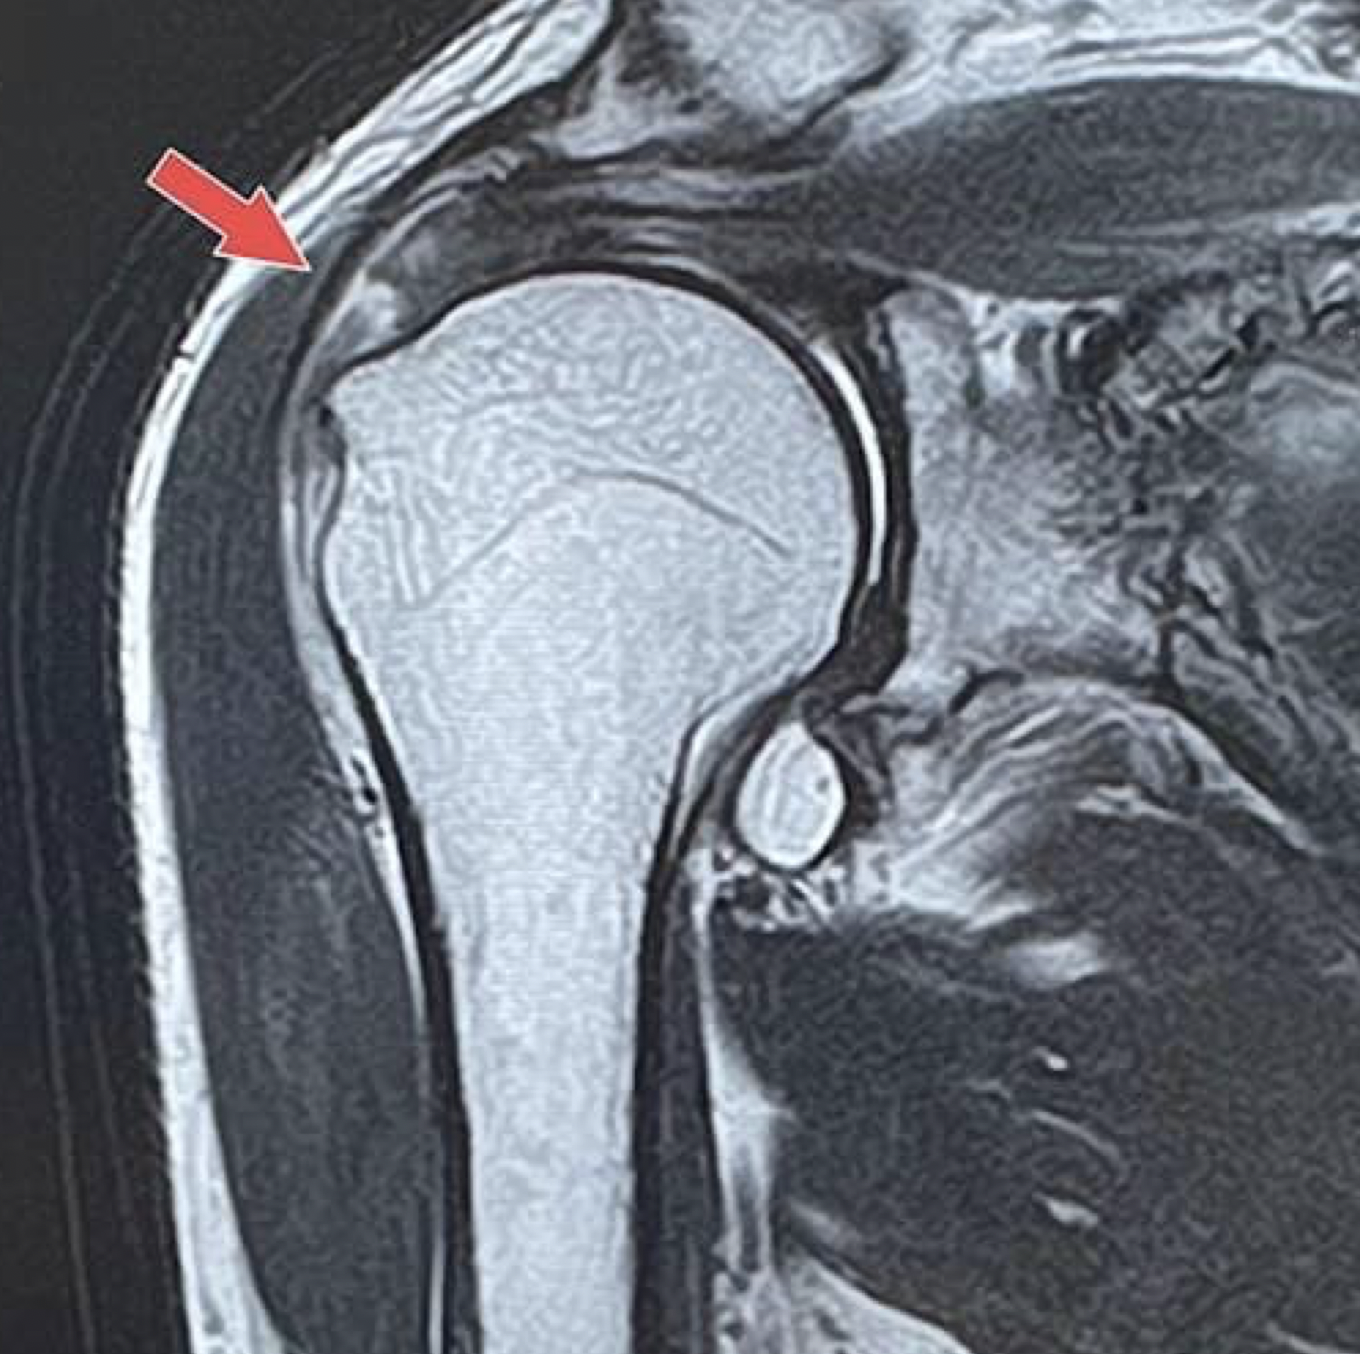

検査時間が短く、高性能、高画質の1.5テスラMRI装置を導入しています。

肩関節